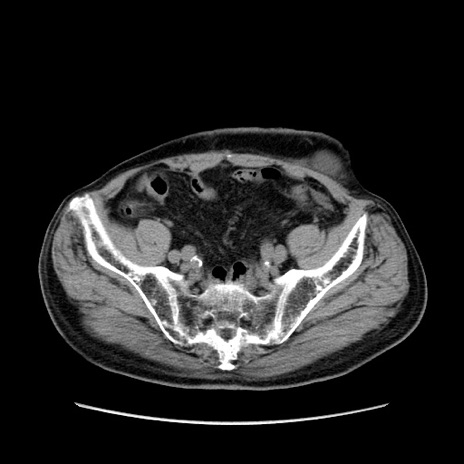

症例24(横断像)

【症例】80歳代男性

【主訴】左側腹部痛、嘔吐

【現病歴】本日早朝より左腹部に痛みあり。昼頃嘔吐認めたため、救急要請。

【既往歴】直腸癌(Mile手術)、胆摘

【身体所見】意識清明、BT 35.9℃、BP 221/93mmHg、SpO2 97%(RA) 、腹部:左ストーマ周囲に限局性の腹部膨隆あり。 膨隆部自発痛・圧痛あり・軟。

【データ】WBC 7700、CRP 0.09